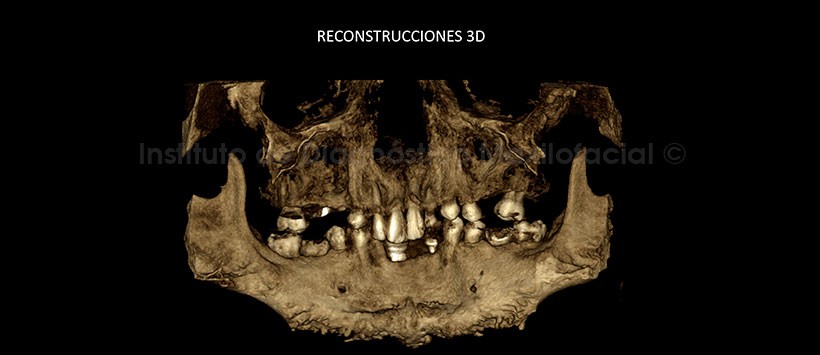

En las reconstrucciones 3D se observa claramente las imágenes antes descritas y su relación con estructuras adyacentes. (Figuras 4, 5, 6 y 7).

Al estudio mediante tomografía computarizada de haz cónico (CBCT), mediante cortes axiales (Figura 2) y coronales (Figura 3) se evidencia la alteración del patrón de trabeculado ósea, que ocasiona la deformación de los mismos, además de la presencia de implantes dentales en el sector ántero inferior.